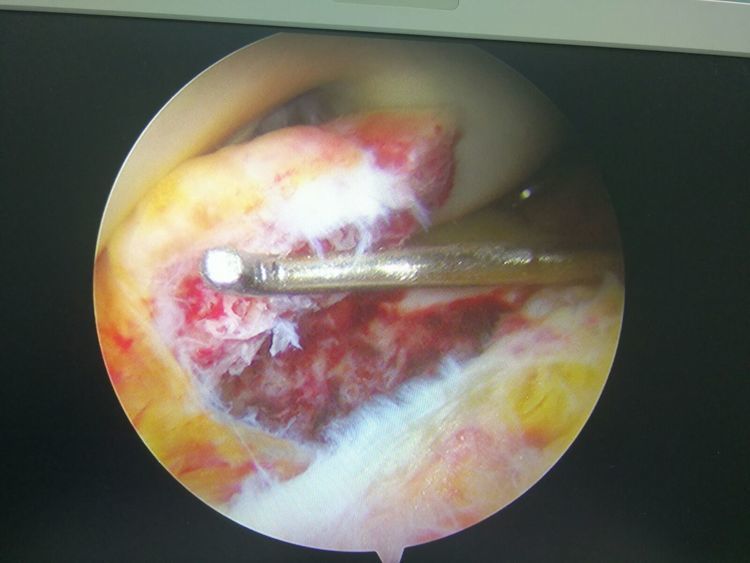

7、 关节镜可施行以往开放性手术难以完成的手术,如半月板部分切除术,肩关节盂唇撕裂修复,踝距骨软骨损伤清理及微骨折手术等。

镜下手术图片,展示人体关节镜下情况:

骨科中心近两年共收治关节镜手术病人500余人,本人在近半年共收治关节疾病患者70余人,包括肩关节脱位及盂唇损伤、半月板损伤、交叉韧带损伤、叉韧带止点撕脱、髌骨脱位、色素性滑膜炎、关节游离体、老年骨性关节炎、踝关节外侧副韧带损伤伴距骨软骨损伤等。均通过关节镜或辅助关节镜手术治疗,短期内随访效果好,总体满意率在95%以上。

特别值的一提的是关节镜清理和韧带松解辅助关节腔注射治疗老年膝关节骨性关节炎效果明显,术后患者膝关节疼痛明显减轻,提高了生活质量,延缓了疾病的进展。当然术前查体及适应症的选择十分重要,患者的信任及配合,术前教育和术后康复指导也都是十分重要的。远期效果我会把随访结果分享给大家,希望大家共同关注老年膝关节骨性关节病!